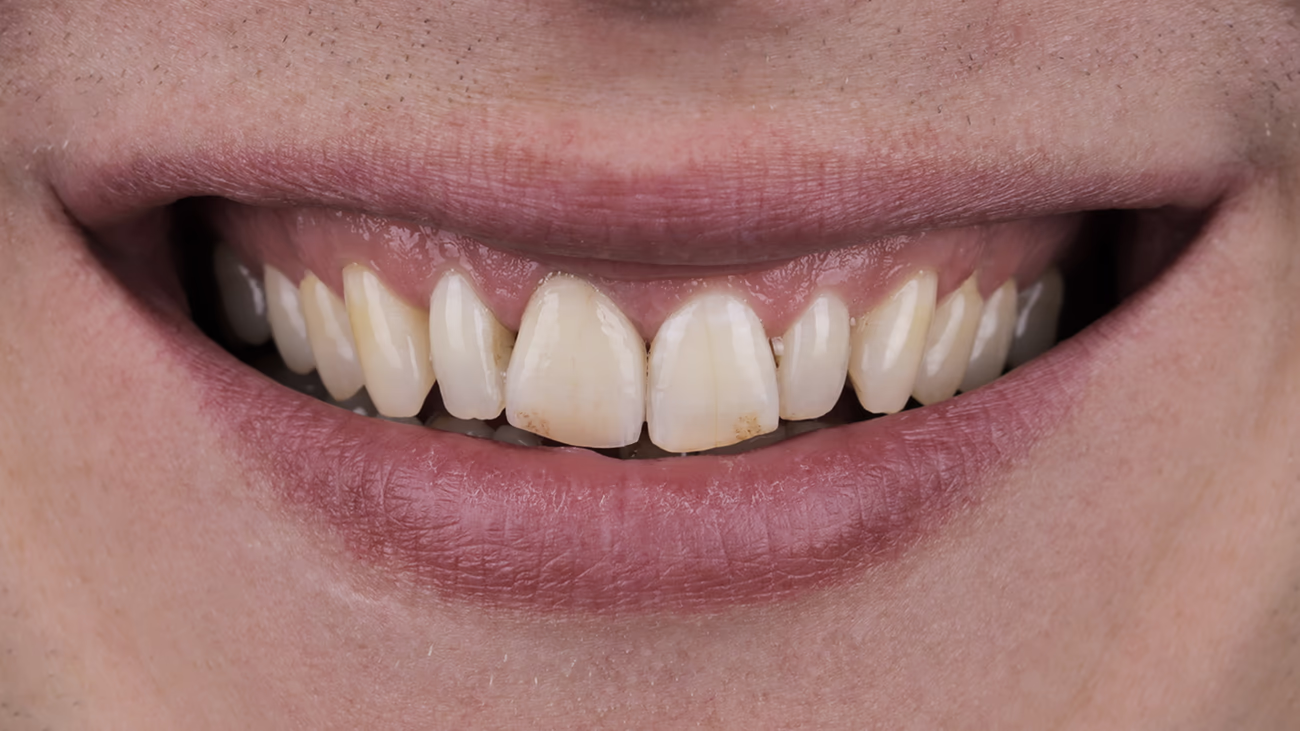

Реабілітація пацієнтів в естетично значущій зоні потребує особливої точності та уваги до деталей. До них належать підбір кольору та яскравості, форма реставрації і стан м’яких тканин.

З метою максимального збереження інтактних тканин вирішено робити втручання лише в межах одного центрального різця 11. Таке завдання складніше для лікаря та зубного техніка, проте дозволяє досягти необхідного естетичного результату при мінімальному обсязі втручання.

Під час відновлення одного зуба ключовим фактором успіху є точна та гармонійна оптична інтеграція реставрації у природний зубний ряд.

Переконавшись, що керамічна реставрація задовольняє естетичний запит пацієнта та стоматолога, можна братися до адгезивної фіксації.

Після фіксації реставрації зробили контрольні фотографії з використанням поляризаційного фільтра та без нього.

Протокол eLAB став ключовим інструментом для досягнення точної колірної відповідності та бездоганної естетики. Чітка цифрова передача даних та злагоджена робота лікаря і зубного техніка дозволяють передбачувано інтегрувати окрему керамічну реставрацію в зубний ряд та відтворювати гармонію усмішки навіть у найскладніших клінічних випадках.